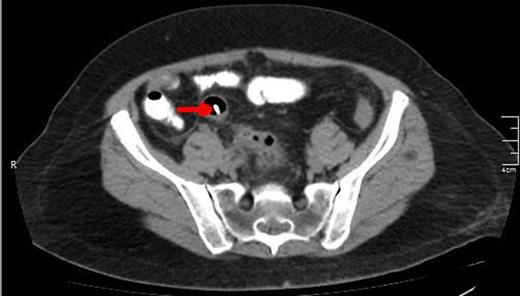

A CT scan showing the upper edge of the biliary stent perforating the antimesenteric surface of the sigmoid colon (red arrow).